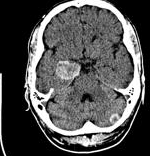

A 77 year old man with known history of metastatic melanoma, confirmed by PET/CT presents witha 2 cm. brain mass. He declines additional systemic treatment.

This is a melanoma. The patient is symptomatic.